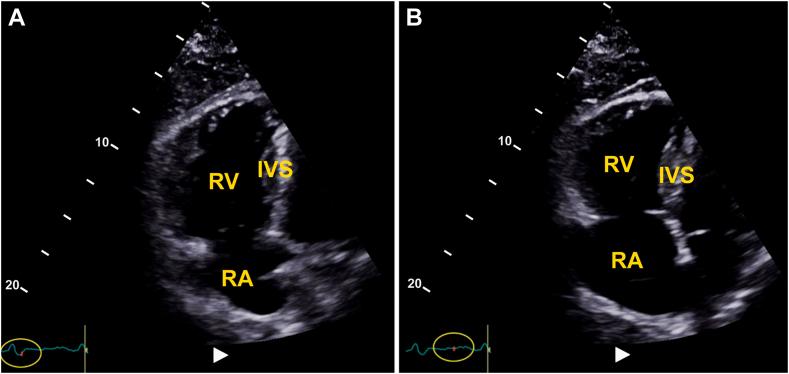

多条探索之路:超声心动图医师对动态血栓的见解——一个超声心动图病例系列

Many Roads Traveled: Sonographer Insights on Clots in Transit-An Echocardiography Case Series.

• CITs are dynamic thrombi in the heart with significant embolic risks. • Echocardiography is essential for detecting CITs and right ventricular dysfunction. • Skilled sonographers optimize imaging using advanced techniques. • Sonographers’ real-time interpretation and communication guide treatment.

摘要

• 心脏内的心脏内血栓(CITs)是具有重大栓塞风险的动态血栓。

• 超声心动图对于检测CITs和右心室功能障碍至关重要。

• 技术娴熟的超声检查人员使用先进技术优化成像。

• 超声检查人员的实时解读和沟通指导治疗。